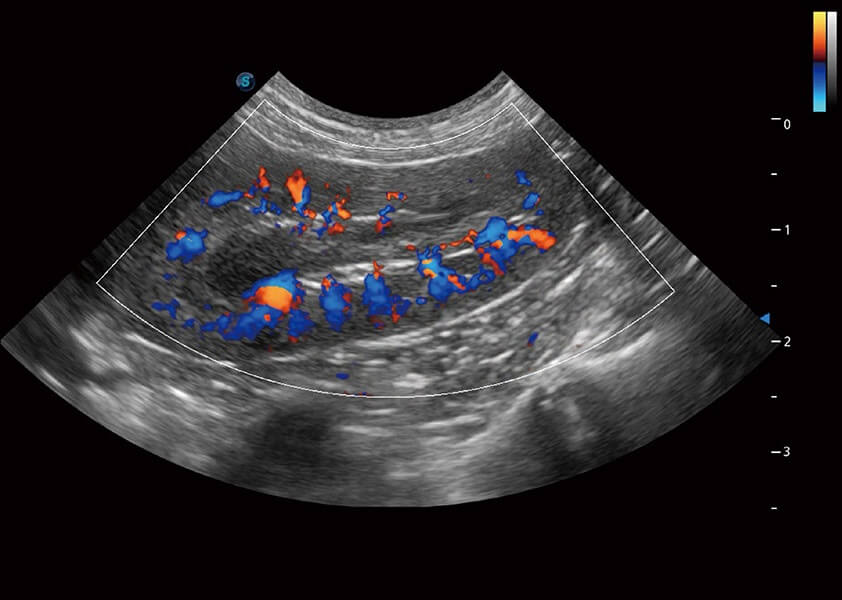

ProPet 60 作為一款高端臺(tái)式動(dòng)物超聲設(shè)備,為動(dòng)物醫(yī)生的日常診斷提供了一系列貼合動(dòng)物臨床需求、解決臨床實(shí)際問(wèn)題的高級(jí)成像功能。憑借全系列高清探頭,滿足醫(yī)生對(duì)腹部、心臟、生殖、淺表、肌骨等成像的所有需求,切實(shí)幫助您提升檢查效率,提高診斷信心。